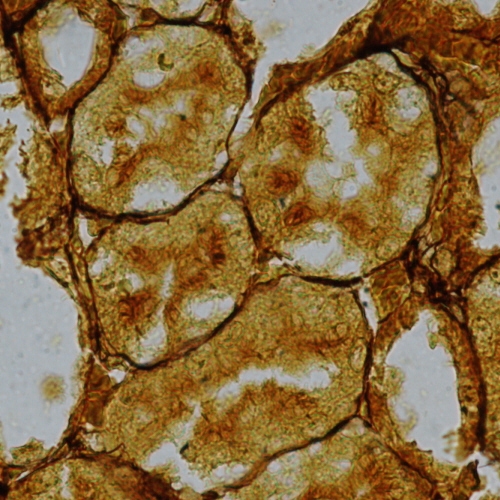

• Brown adipose tissue

• Prominent in newborn of all mammals

• In adults most conspicuous in species which hibernate

• Present in man throughout life

• Cells are smaller than those of white adipose tissue

• Cytoplasm relative abundant and contains lipid droplets of varying size

• Cytoplasm contains extraordinary large number of mitochondria

• Brown fat has a lobular organization

• Highly vascular with blood vessel distribution similar to that of a gland

• Numerous small unmyelinated nerves with axons ending on cell surface